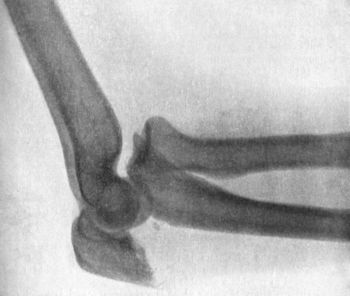

| 36. | Backward Dislocation of Elbow in a Boy | 89 |

| 37. | Bony Outgrowth in relation to insertion of Brachialis Muscle | 90 |

| 38. | Radiogram of Incomplete Backward Dislocation of Elbow | 91 |